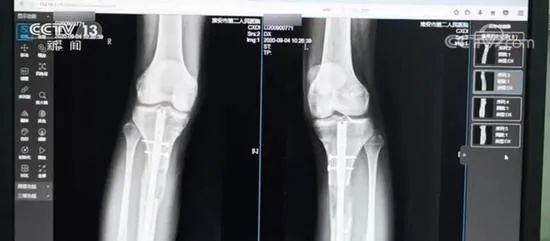

增高术前人为制造的“骨折”(图源:视频截图)